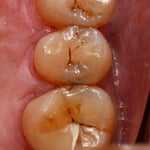

一番左の写真で、どこに虫歯があるかわかるでしょうか?虫歯の進展度を知るためにはレントゲンは欠かせませんが、レントゲンを撮影しなくても、自然光に近い明るい視野の下で、拡大してじっくり観察すれば、早期発見、早期治療に最も役立つのが顕微鏡です。これも当院のベテラン衛生士が最初に気付いた虫歯です。自覚症状がでてからでは、歯髄を保存できる可能性が低くなってしまいます。この症例も、歯髄を除去ぜす(根管治療をしないで)保存できました。

自然光に近い明るい光の下で、拡大して、じっくり観察しなければ、早期に発見出来ない虫歯が多いのです。